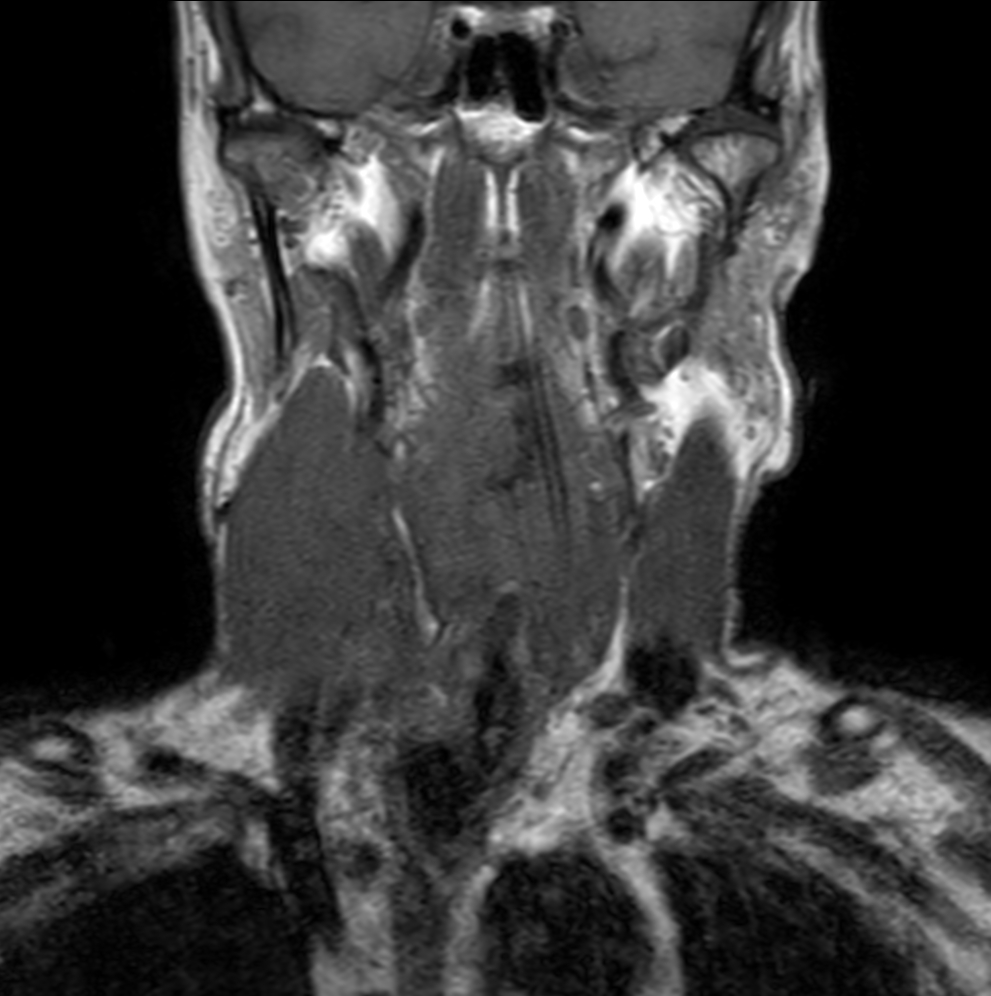

Coronal STIR TSE